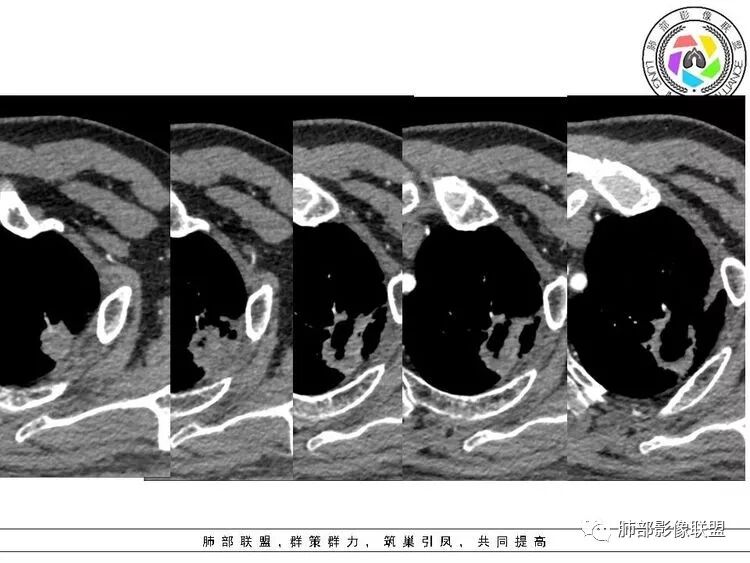

1.左肺上叶应为空腔样病灶。如作为空洞,前下壁并不完整,且与薄壁囊腔壁相延续,整体结合起来看应为厚薄不均匀的较大的空腔样病灶。这样的空腔样病灶应首先怀疑空腔性肺癌。

3.病灶轻度环形强化,壁稍显僵硬。灶周显示较清楚,未见磨玻璃晕。

5.吸烟老年男性患者,临床表现轻微。

空腔性肺癌主要见于腺癌和鳞癌,上述2-5项更倾向鳞癌。

病理上在肺纤维化蜂窝区和相邻肺气肿交界区域常常会观察到肺泡上皮反复增生及支气管上皮鳞状细胞化生,然后通过不典型增生最后导致细胞恶性转化。并且有人认为且肺纤维化瘢痕可以导致淋巴管阻塞,局部潜在致癌物质增多,使得在该背景下容易发生肺癌。所以即使病灶形状不一定呈肿瘤样膨胀生长,但位于局限的肺气肿与肺纤维化交界区也需谨慎观察。